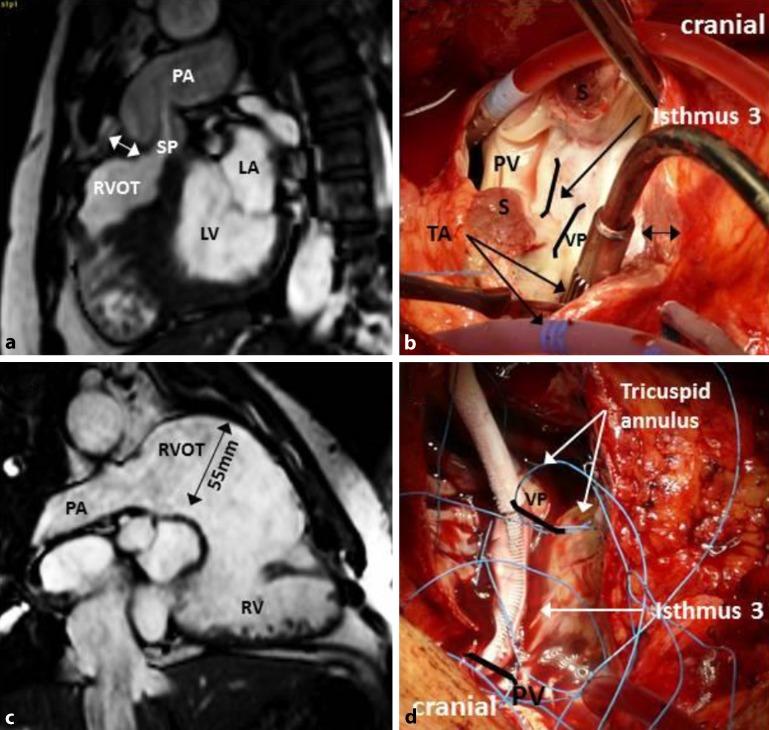

Ventricular arrhythmias are an important cause of late morbidity and sudden cardiac death in the growing population of adults with repaired congenital heart disease. Risk stratification remains challenging because of the heterogeneity of the malformations and the surgical approaches. Therapeutic interventions depend on the type of ventricular arrhythmia, which can be polymorphic ventricular tachycardia (VT) or ventricular fibrillation in patients without ventricular scars, but also potentially fatal monomorphic reentrant VTs, typical for patients with ventricular scars or obstacles. Advances in surgical techniques have improved survival and have important implications for the arrhythmia substrates and prognosis. Over the past few decades, progress has been made to determine the anatomical basis for monomorphic VT in patients with ventricular surgical scars and patch material. These substrates can be currently identified and targeted during sinus rhythm by radiofrequency catheter or surgical ablation without the need for VT induction. The review provides an update on the evolving surgical approaches, the changing VA substrates, and the potential consequences for individualized risk assessment and tailored treatment.